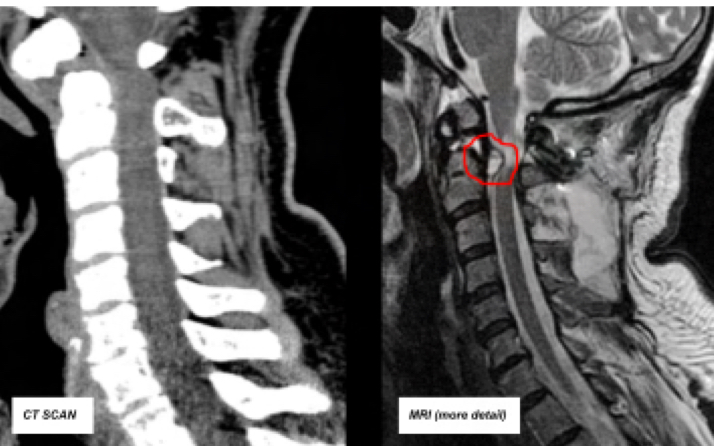

What are MRI sequences

Different programs that aid in viewing specific areas